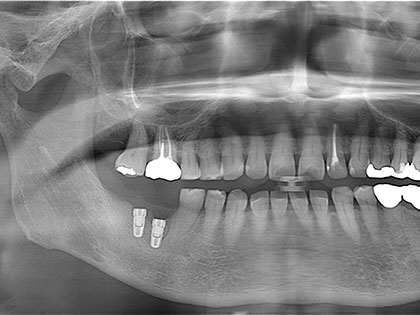

治療中の写真がこちら

治療完了時の写真がこちら

治療完了時の

写真がこちら

治療期間

8か月

治療回数

8回

治療内容

右下6、7 インプラント

リスク・

副作用

定期的メンテナンスが必要。汚れがたまると歯周炎になるリスクあり。